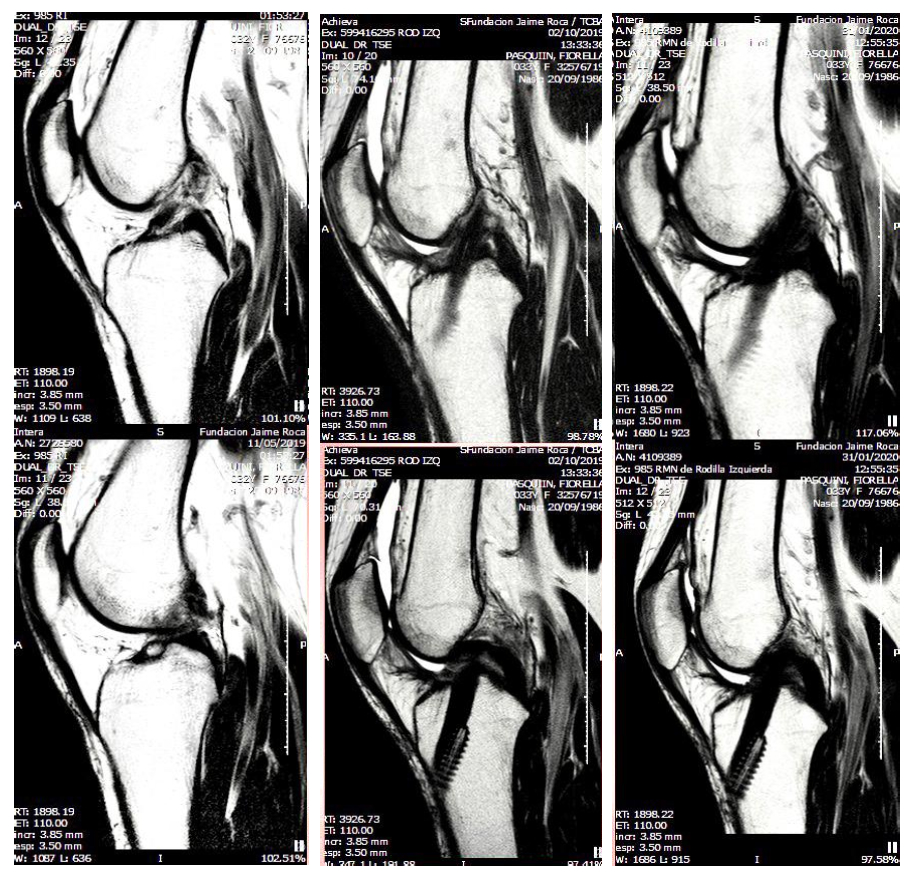

De izquierda a derecha: en la primera columna se observa la lesión en ligamento cruzado, en la segunda el postquirúrgico y en la tercera columna, se muestra ya lista para la vuelta al deporte.

La ruptura de LCA puede sospecharse por algunas maniobras semiológicas y confirmarse mediante una Resonancia Magnética de la rodilla afectada.

La Resonancia de Rodilla para evaluar lesiones ligamentarias y Rx para descartar lesiones óseas asociadas.